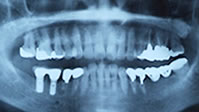

2本の白いセラミック冠が入りました

入れ歯でなく自分の歯と同じように噛めるようになりました

リコール時のX線像です